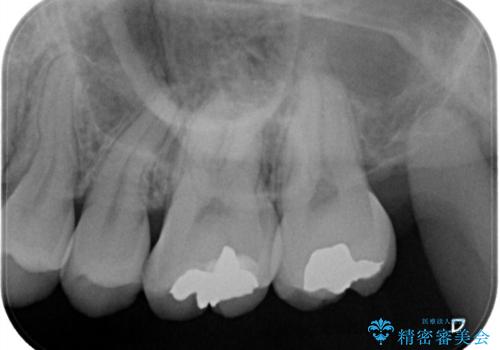

- 奥歯の銀歯が目立つということで来院されました。もともと入っていた銀歯を取り、虫歯の治療を行い、型取りを行ないます。

よく銀歯の下が虫歯になっていることがあります。

今回の患者様も銀歯を取ってみたら大きな虫歯になっていました。